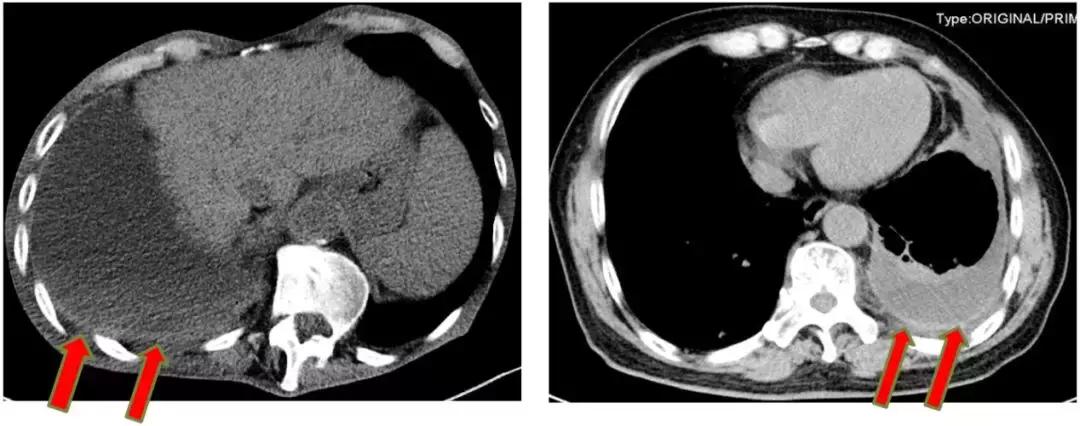

4、邻近脏器损伤

个别情况下,穿刺针位置较低等原因造成误穿肝脏、脾脏、肾脏等邻近脏器。

患者可能无明显症状,而病理检查发现送检的为肝、脾或肾组织。如果刺伤脏器较明显,尤其是较脆弱且易出血的脾脏,可能会导致大出血而需要手术处理。